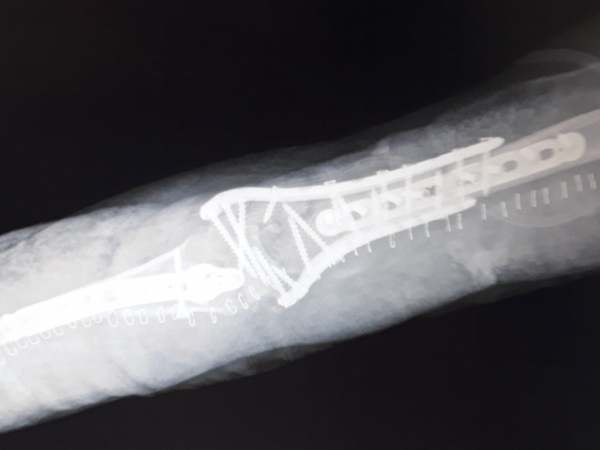

Images Gallery